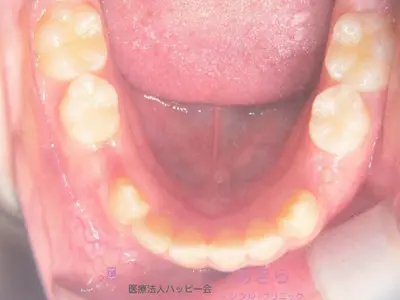

初診時

case-001-7